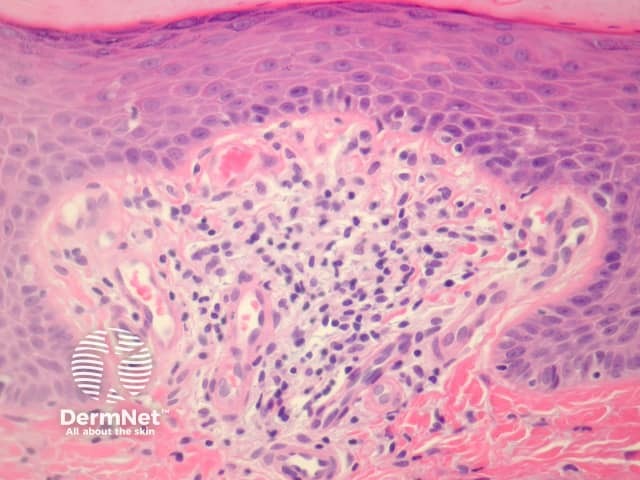

In Flegel disease, sections show discrete zones of compact lamellar hyperkeratosis with focal parakeratosis (figure 1). The epidermis under the hyperkeratosis is atrophic compared with the surrounding skin, and the granular layer is attenuated absent (figure 2). The papillary dermis contains a dense band-like infiltrate composed of small lymphocytes intermingled with histiocytes. Vasodilation of superficial vessels is also seen (figure 3).

Figure 3